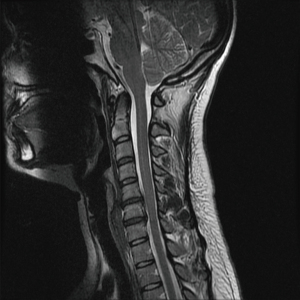

The patient was identified on physical examination to have diminished sensation in the right fourth and fifth finger (C8) and the left shoulder, radial aspect of forearm, thumb, index finger, and middle finger (C5 and C6). The reflex examination was 2+ throughout except for the left biceps and triceps which were 3+. The patient had 5/5 strength in all muscle groups in the upper and lower extremities. There was tenderness of the paraspinal musculature posteriorly. The patient had limited range of motion on account of pain in the neck. Patient was determined to have cervical disc disease with disk disease associated with C5–C6 and C6–C7 (Figures 1,2).

Figure 1 T2 sagittal magnetic resonance imaging demonstrating herniated disc of C5–C6 and C6–C7.